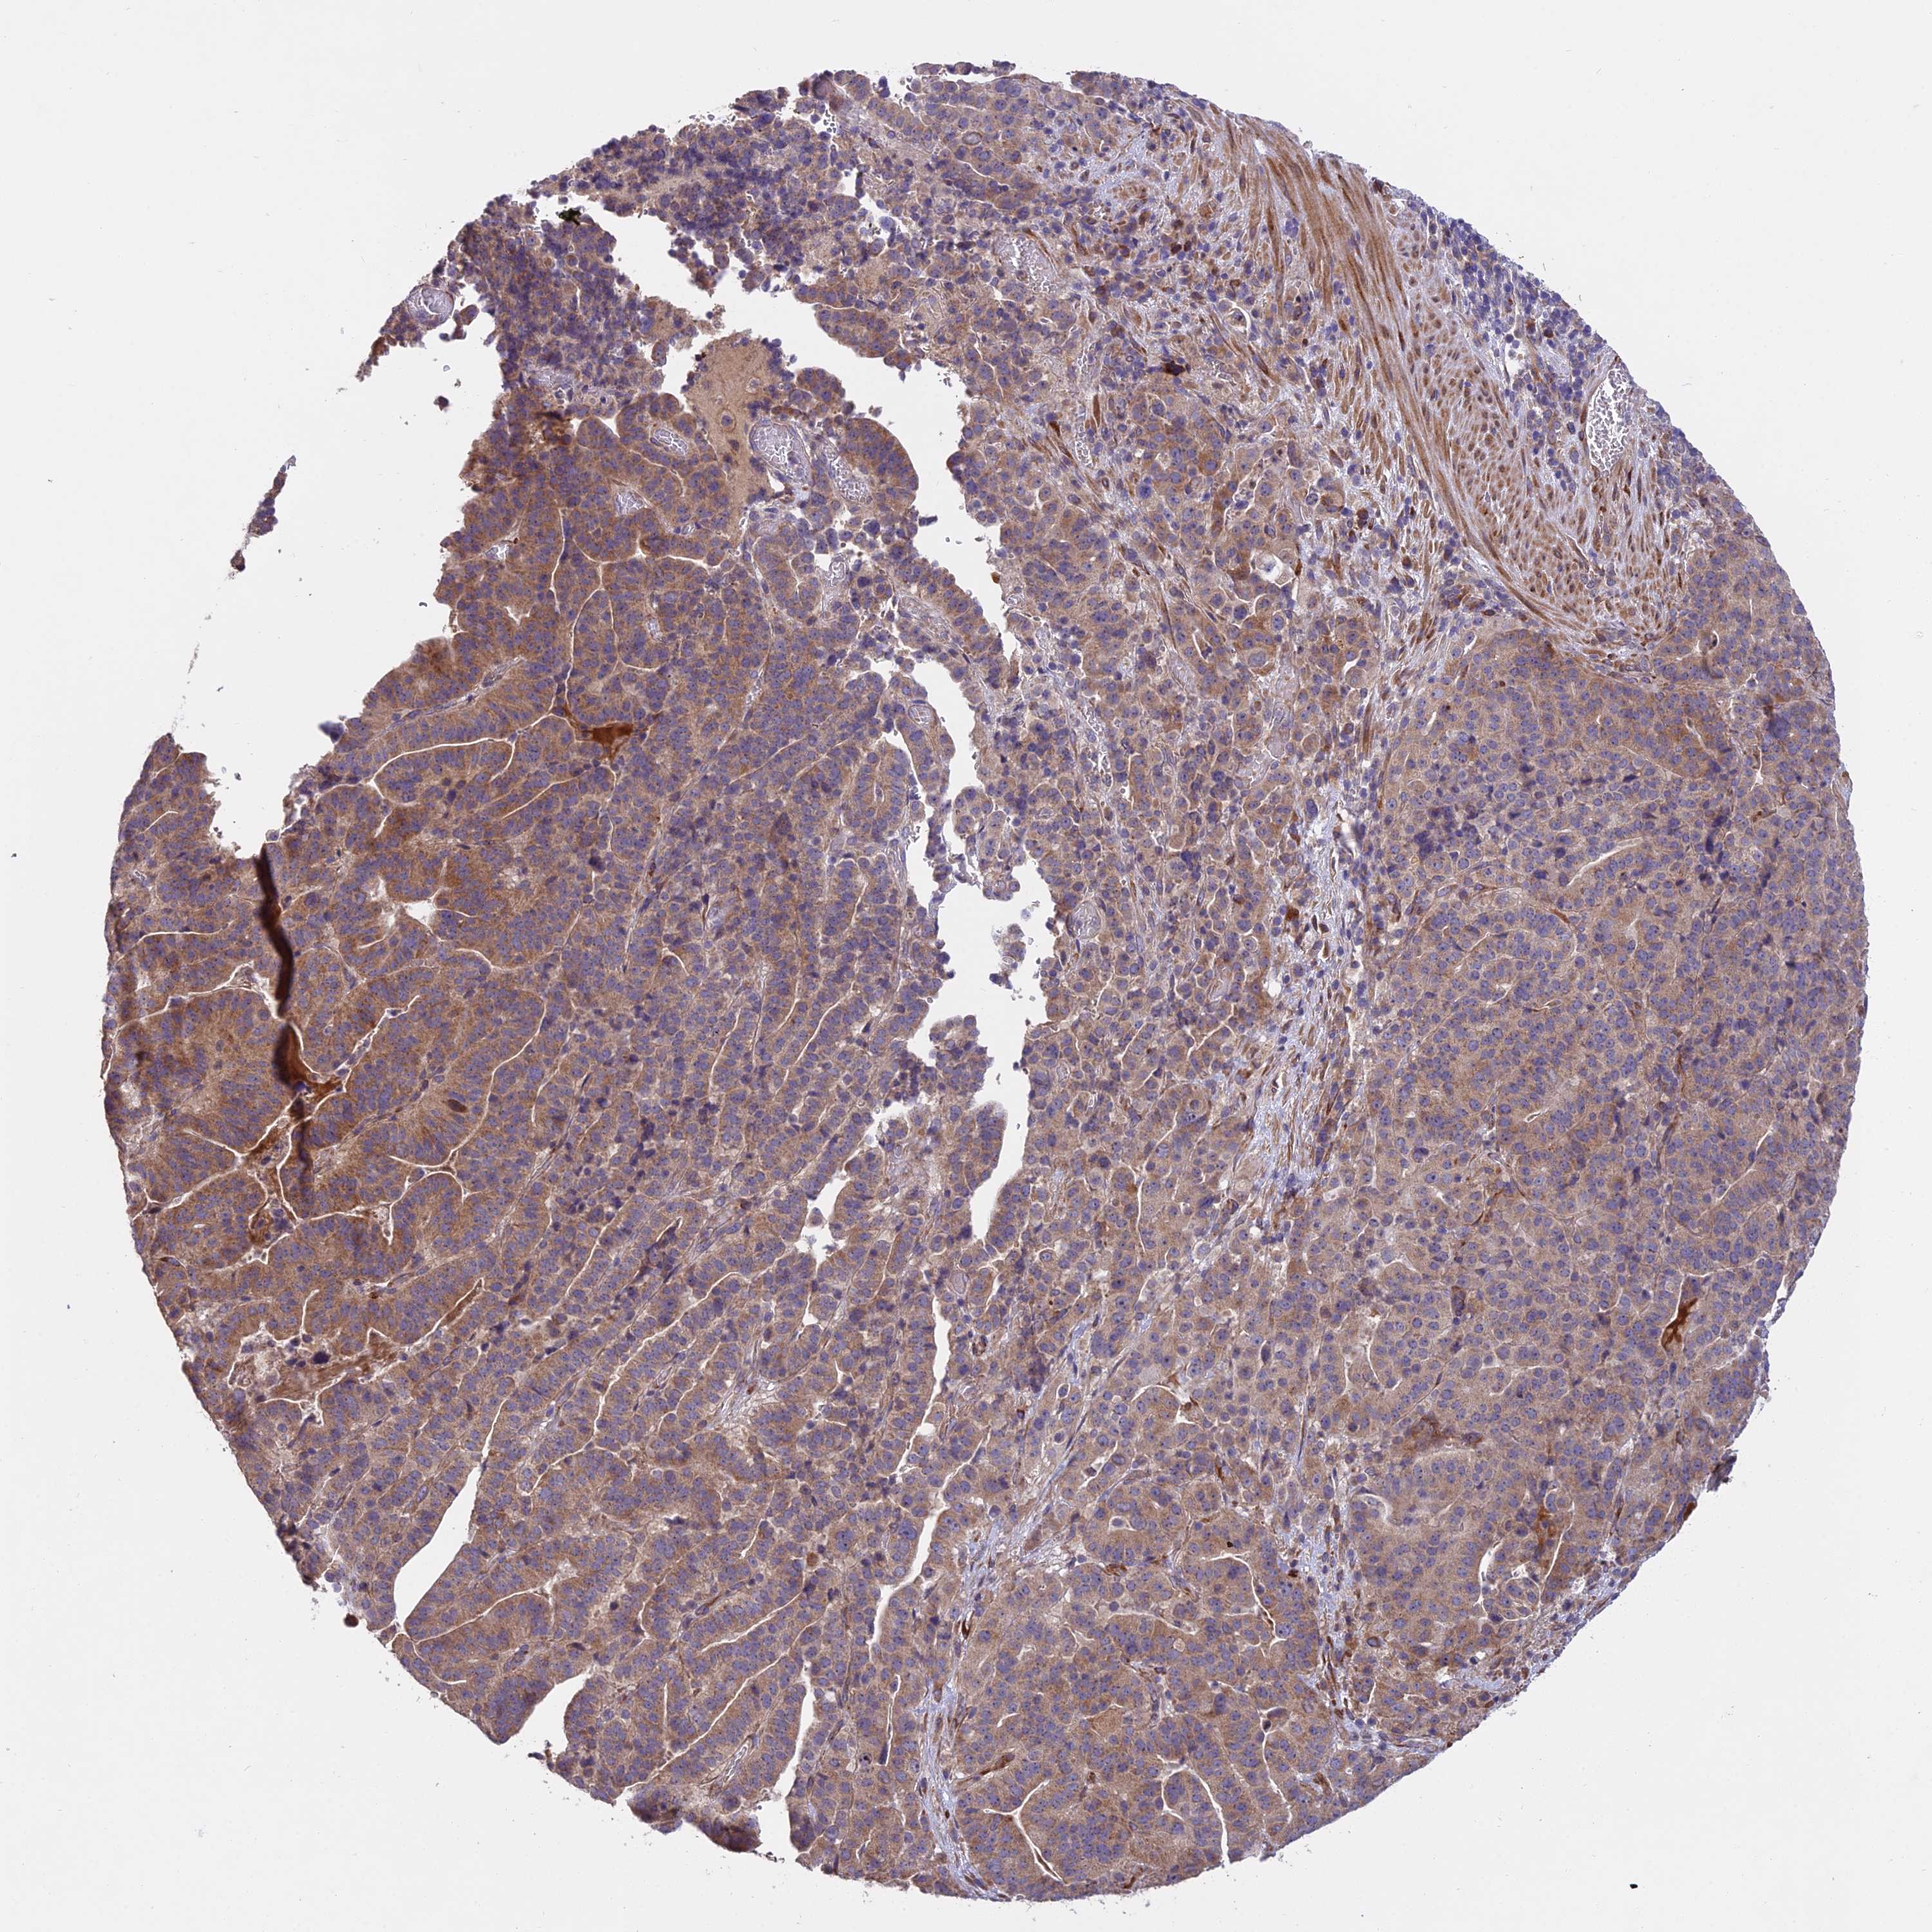

STOMACH CANCER - Protein expressioni

A mouse-over function shows sample information and annotation data. Click on an image to view it in a full screen mode. Samples can be filtered based on level of antibody staining by selecting one or several of the following categories: high, medium, low and not detected. The assay and annotation is described here.

Note that samples used for immunohistochemistry by the Human Protein Atlas do not correspond to samples in the TCGA dataset.

Antibody stainingi

Antibody staining in the annotated cell types in the current human tissue is reported as not detected, low, medium, or high, based on conventional immunohistochemistry profiling in selected tissues. This score is based on the combination of the staining intensity and fraction of stained cells.

Each image is clickable and will lead to virtual microscopy that enables deeper exploration of all samples and also displays staining intensity scores, fraction scores and subcellular localization as well as patient and tissue information for each sample.

Antibody HPA044520

Staining

High

Medium

Low

Not detected

Intensity

Strong

Moderate

Weak

Negative

Quantity

>75%

75%-25%

<25%

None

Location

Nuclear

Cytoplasmic/membranous

Cytoplasmic/membranous,nuclear

Adenocarcinoma, NOS